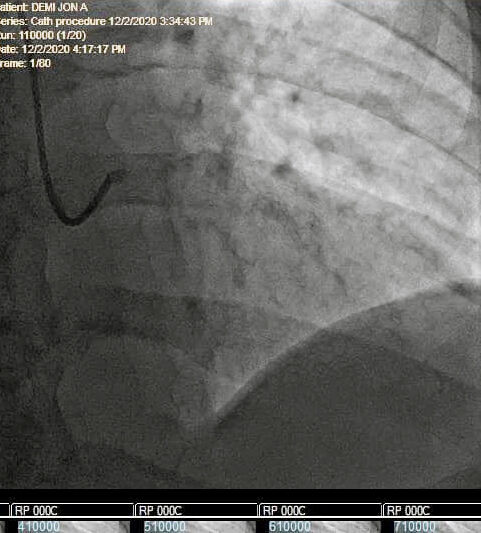

Demi said Dr. Jose Venero, a Washington Health Systems cardiologist, performed an initial cardiac catheterization to try to determine the cause of Demi’s pain, but the location of the twist in the artery made it undetectable. After the procedure, Demi was still in pain, even with morphine, he said.

Demi said Venero went over the sonogram again and saw an area of his heart where “there wasn’t as much activity as normal.” Venero, Demi said, decided to “go back in” and check it out.

“In what I can only describe as him being guided by the hand of God, he was able to probe the area where he thought the blockage might be, open the artery and put a stent in to keep it from twisting again without puncturing or perforating my artery,” Demi wrote in a Facebook post two days after the procedure.